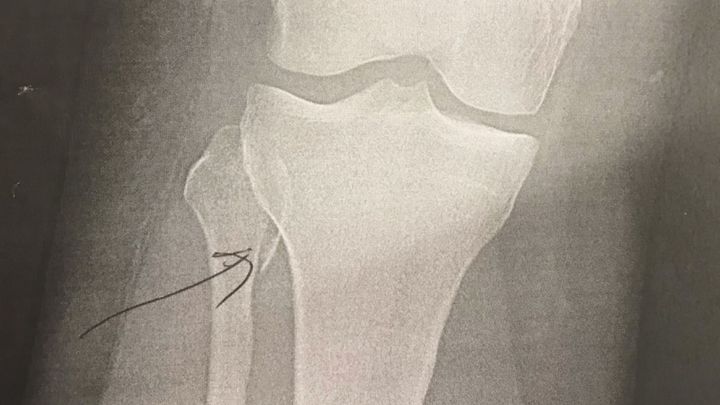

As most of you know I broke my leg 2 days into my vacation which started in November. Upon coming home, I received an MRI and a diagnosis that my ACL was completely ruptured. After 5 initial weeks of therapy, it was decided that I needed to go into surgery to have my ACL replaced.